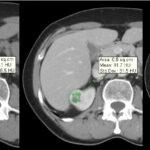

Fase excretora o arterial tardía

Comienza aproximadamente a los 3 minutos posteriores a la inyección del medio de contraste y permite evaluar su excreción por el sistema colector; por lo tanto, es útil para evaluar la relación de la masa con los cálices y la pelvis renal y llegar a una mejor planificación quirúrgica conservadora en un caso dado 3-4 (Fig. 4).